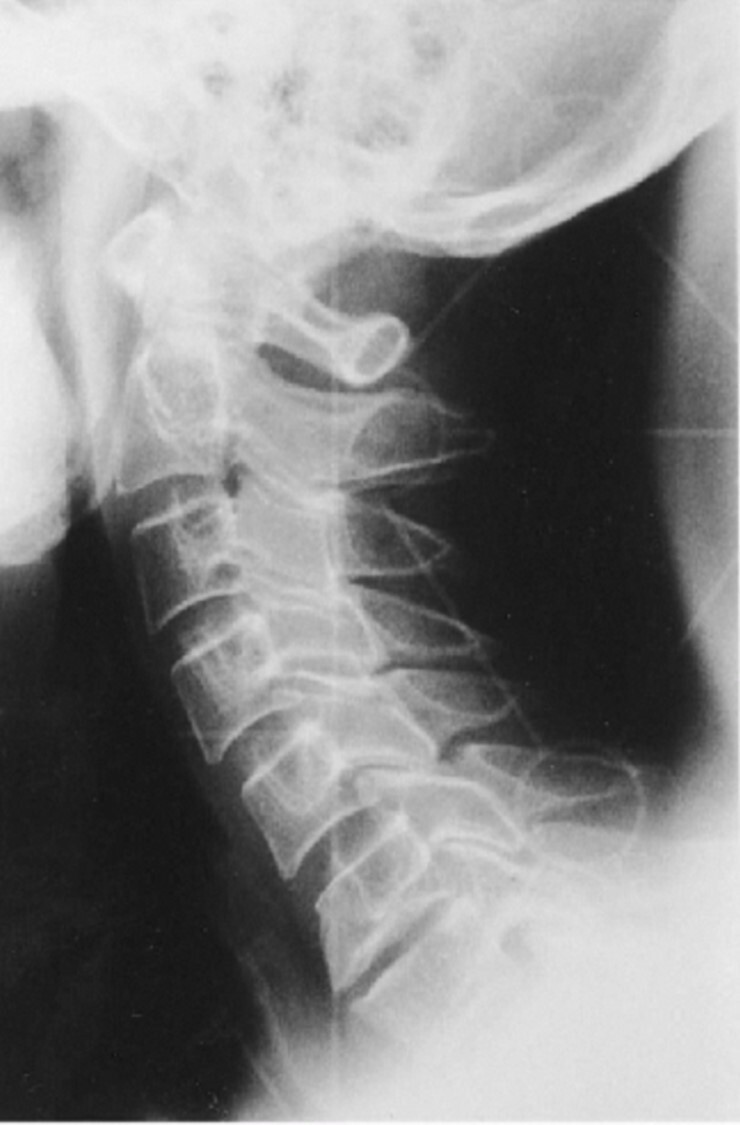

Q

What is the cause of the artifact seen in the attached image captured on a CR plate?

A

Exposure through the back of the CR plate